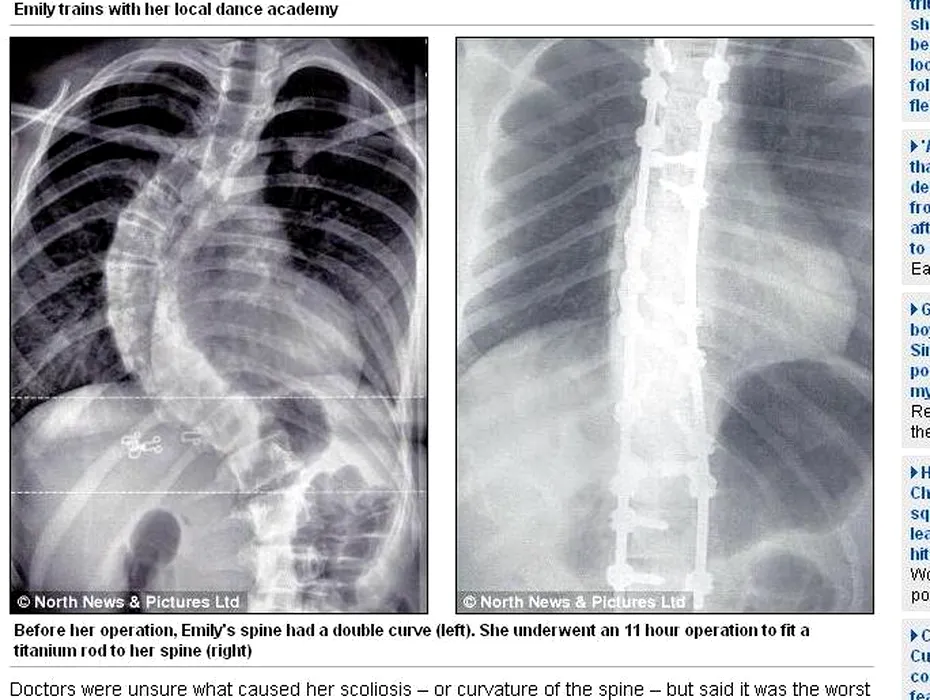

Medicii britanici au fost uimiți când au văzut radiografia unei fete de 13 ani: „Este cel mai grav caz pe care l-am întâlnit”